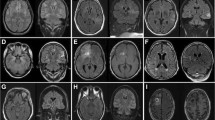

A female patient was referred for epilepsy surgery at 3.5 months of age because of medically refractory epilepsy since the first day of life due to left-sided frontotemporal cortical dysplasia (Fig. 1a–c). Long-term EEG video monitoring on the ICU showed left hemispheric seizure patterns. She received multiple trials of ASMs (valproic acid, oxcarbazepine, phenobarbitone, phenytoin, vigabatrin, levetiracetam, topiramate, lacosamide) and was placed on a ketogenic diet without significant seizure relief. Eventually, the seizures increased in number (80–160/day, Fig. 2) and evolved into RSE requiring HDST with midazolam. The need for catecholamine supply, central venous catheter, and mechanical ventilation were considered HDST-related morbidities. After left functional hemispherotomy (Fig. 3), RSE was terminated and she was finally discharged with ASM. However, 2 months after surgery, seizures reoccurred and were again refractory to ASM although there was no progression to SE. A second operation was performed 6 months after the first operation and included complete disconnection, which was not achieved during the first surgery. The patient remains seizure free since the second operation with one ASM at a follow-up period of 4 years and has shown significant neurodevelopmental gains. Surgery-related morbidity comprised right-sided spastic hemiplegia, right-sided hemianopia, and central diabetes insipidus.